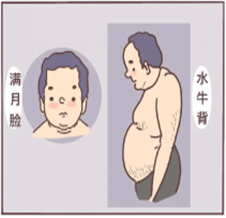

②分泌皮质醇的腺瘤:可能引起“库欣综合征”,表现为向心性肥胖(肚子大、四肢瘦)、满月脸(脸变圆)、背变厚(水牛背),痤疮、皮肤紫纹,还可能伴随血糖升高、骨质疏松。